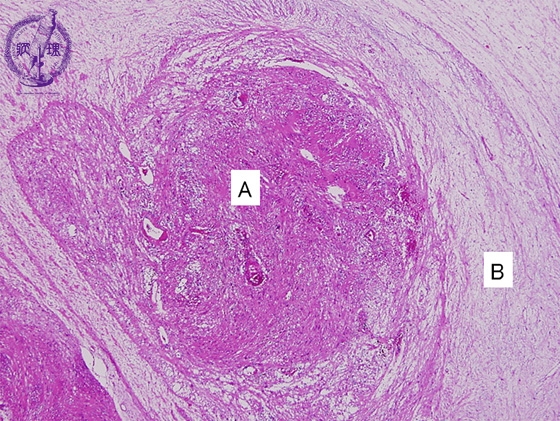

- ★(2)Schwannoma

Microscopic findings (H.E. low power view): Thecoexistence of cellular Antoni A area associated with proliferation of spindle cells and edematous Antoni B area associated with scattered spindle cells.